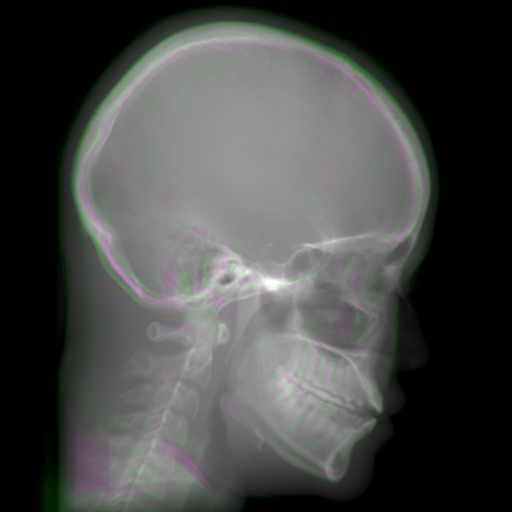

Refer to caption

(a) Orthogonal 0superscript00^{\circ}

(b) Perspective 0superscript00^{\circ}

(c) Perspective deformation ((b)-(a))

(d) Perspective 180superscript180180^{\circ}

(e) Difference of Perspective 0superscript00^{\circ} and 180superscript180180^{\circ}

(f) RGB 0superscript00^{\circ} and 180superscript180180^{\circ}

Figure 6: An example for perspective deformation learning from dual complementary views: (a) the orthogonal projection of the 3D bead phantom from the 0superscript00^{\circ} view; (b) the perspective projection from the 0superscript00^{\circ} view; (c) the difference image between (b) and (a); (d) the perspective projection from the 180superscript180180^{\circ} view; (e) the difference image between (d) and (b); (f) the RGB stack of the 0superscript00^{\circ} and 180superscript180180^{\circ} perspective projection images, where the magenta and green areas correspond to the positive (bright) and negative (dark) areas in (e). The intensity range [0, 11] is converted to [0, 255] for visualization.

Note that when and only when z=0𝑧0z=0, which is m=m=1superscript𝑚𝑚1m^{\prime}=m=1, d180subscript𝑑superscript180d_{180^{\circ}} and dPDsubscript𝑑PDd_{\text{PD}} both equal to 0. This provides a practical way to observe which structures suffer from perspective deformation by assessing deviations between the two complementary views.

The orthogonal and perspective projection images of the same 3D bead phantom in a complementary view setting are displayed in Fig. 6. Fig. 6(c) shows the perspective deformation, which is the difference between the perspective projection (Fig. 6(b)) and the orthogonal projection (Fig. 6(a)) from the 0superscript00^{\circ} view. Fig. 6(c) clearly demonstrates that the magnitude of perspective deformation increases from the center outwards radially. The 180superscript180180^{\circ} perspective projection image is displayed in Fig. 6(d) and its difference with respect to the 0superscript00^{\circ} perspective projection is displayed in Fig. 6(e). Fig. 6(e) is similar to Fig. 6(c) in bead areas, which illustrates that the deviation between two complementary views has strong correlation to perspective deformation. To integrate such dual-view information, like Fig. 5(d), we convert the perspective projections images from the 0superscript00^{\circ} and 180superscript180180^{\circ} views to a 3-channel RGB image in Fig. 6(f). The red and blue channels use images from the 0superscript00^{\circ} view, while the green channel uses images from the 180superscript180180^{\circ} view. In the RGB images, the color reveals the intensity difference between the 0superscript00^{\circ} and 180superscript180180^{\circ} perspective projection images. Grey areas contain close intensity values from both views. Instead, magenta and green areas indicate larger intensity values from the 0superscript00^{\circ} and 180superscript180180^{\circ} views respectively, where perspective deformation correction is necessary. They correspond to the positive (bright) and negative (dark) areas in the difference image in Fig. 6(e). In Fig. 6(f), the magenta beads and their corresponding green beads are located close to each other, which allows a network with limited receptive field size to capture bead-to-bead (point-to-point) dependency.